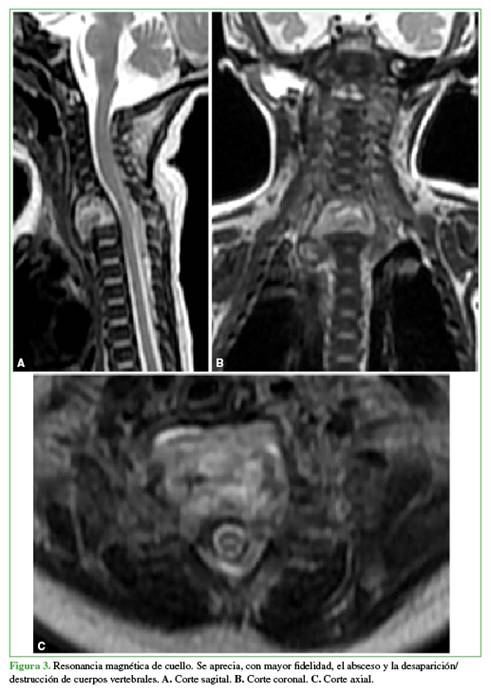

Se visualizó un importante absceso retrofaríngeo y retrotraqueal, asociado a osteólisis de los cuerpos vertebrales cervicales inferiores, con lesión de tipo infeccioso en el raquis cervical inferior y torácico superior. Para completar la evaluación se solicitó una resonancia magnética que confirmó el absceso y la destrucción infecciosa de los cuerpos vertebrales de T1, C7 y C6 (este último parcialmente) (Figura 3).

Si bien la ecografía y la radiología convencional pueden ser de alguna utilidad para el diagnóstico de esta enfermedad, la resonancia magnética de columna es el estudio diagnóstico de elección por su mayor sensibilidad y especificidad. Permite evaluar y diferenciar la destrucción ósea y discal, y delimitar la existencia de abscesos paravertebrales.12 En nuestro caso, el uso de la tomografía computarizada antes de la resonancia se debió a la disponibilidad en la institución; sin embargo, fue muy útil para mostrar la lesión y evaluar la destrucción ósea (Figura 2).